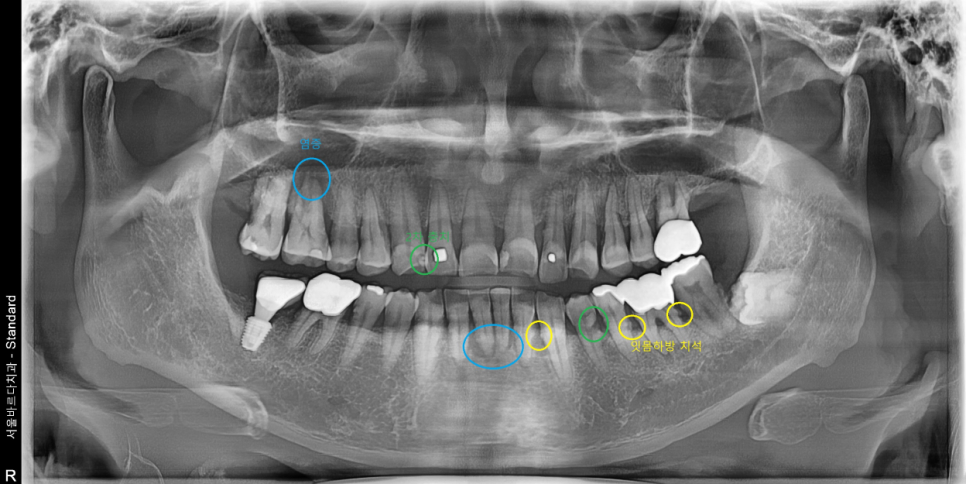

치아의 전반적인 뼈와 치아상태를 확인하는 파노라마 엑스레이 촬영해보니

오른쪽 위 어금니와 아래 앞니 뿌리끝에 염증도 보이고

전체적으로 잇몸 하방에 치석이 많이 있었습니다.

상악 임플란트의 경우 상악동이라는 공기주머니가 얇은 막으로 둘러싸고 있는데요

상악동을 다치게 하지 않으면서 임플란트를 잘 식립을 해야 합니다.